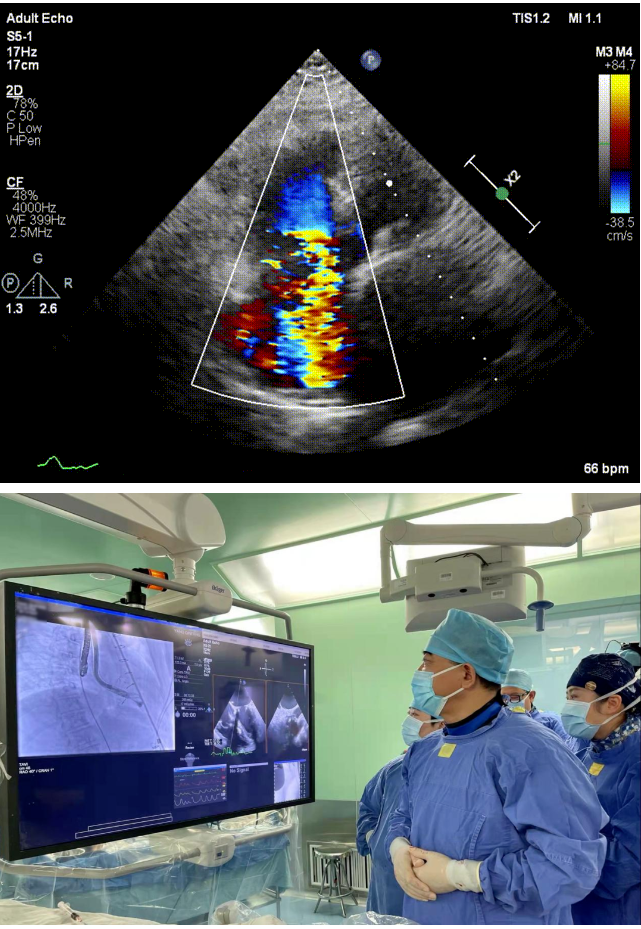

本次接受治療的患者是一名74歲的女性,14年前因風(fēng)濕性心臟病行二尖瓣生物瓣植入術(shù),合并房顫。近3年來反復(fù)因腹脹、納差、下肢水腫入院,藥物治療欠佳。心臟超聲顯示三尖瓣極重度反流(有效反流口面積:0.76cm²,反流容積:79ml),繼發(fā)性右房室增大及上、下腔靜脈增寬(右房上下徑*左右徑:52*41mm,右室左右徑:46mm,下腔靜脈:29mm),右室收縮功能正常,肺動(dòng)脈收縮壓 43mmHg,左心室射血分?jǐn)?shù)73% ?;颊呒韧_胸手術(shù)史,術(shù)前評(píng)估STS 評(píng)分為7.02分,CRS 9分,無法接受體外循環(huán)下三尖瓣外科手術(shù)。面對(duì)這一傳統(tǒng)治療無法解決的困境,葛均波院士及其團(tuán)隊(duì)周達(dá)新教授、潘文志教授、張?jiān)床┦?、陳莎莎博士及心超室的潘翠珍教授、李偉教授?jīng)過討論決定,采用創(chuàng)新的Lux-Valve Plus系統(tǒng)為患者進(jìn)行經(jīng)血管三尖瓣置換。

手術(shù)在患者全麻狀態(tài)下進(jìn)行,采用經(jīng)右側(cè)頸靜脈作為入路,將裝載有人工瓣膜的輸送器緩慢推送至右心房;并在經(jīng)食道超聲和DSA的引導(dǎo)下小心調(diào)整輸送器角度,將輸送器送入右心室;逐步釋放瓣膜錨定裝置和盤片,調(diào)整瓣膜位置后,錨定瓣膜完成植入。術(shù)后右房壓明顯下降,從術(shù)前的25/10(16) mmHg降至術(shù)后即刻的12/7(10) mmHg,術(shù)后超聲提示人工三尖瓣同軸性良好,固定牢固,無反流及瓣周漏,手術(shù)室即刻拔除氣管插管。